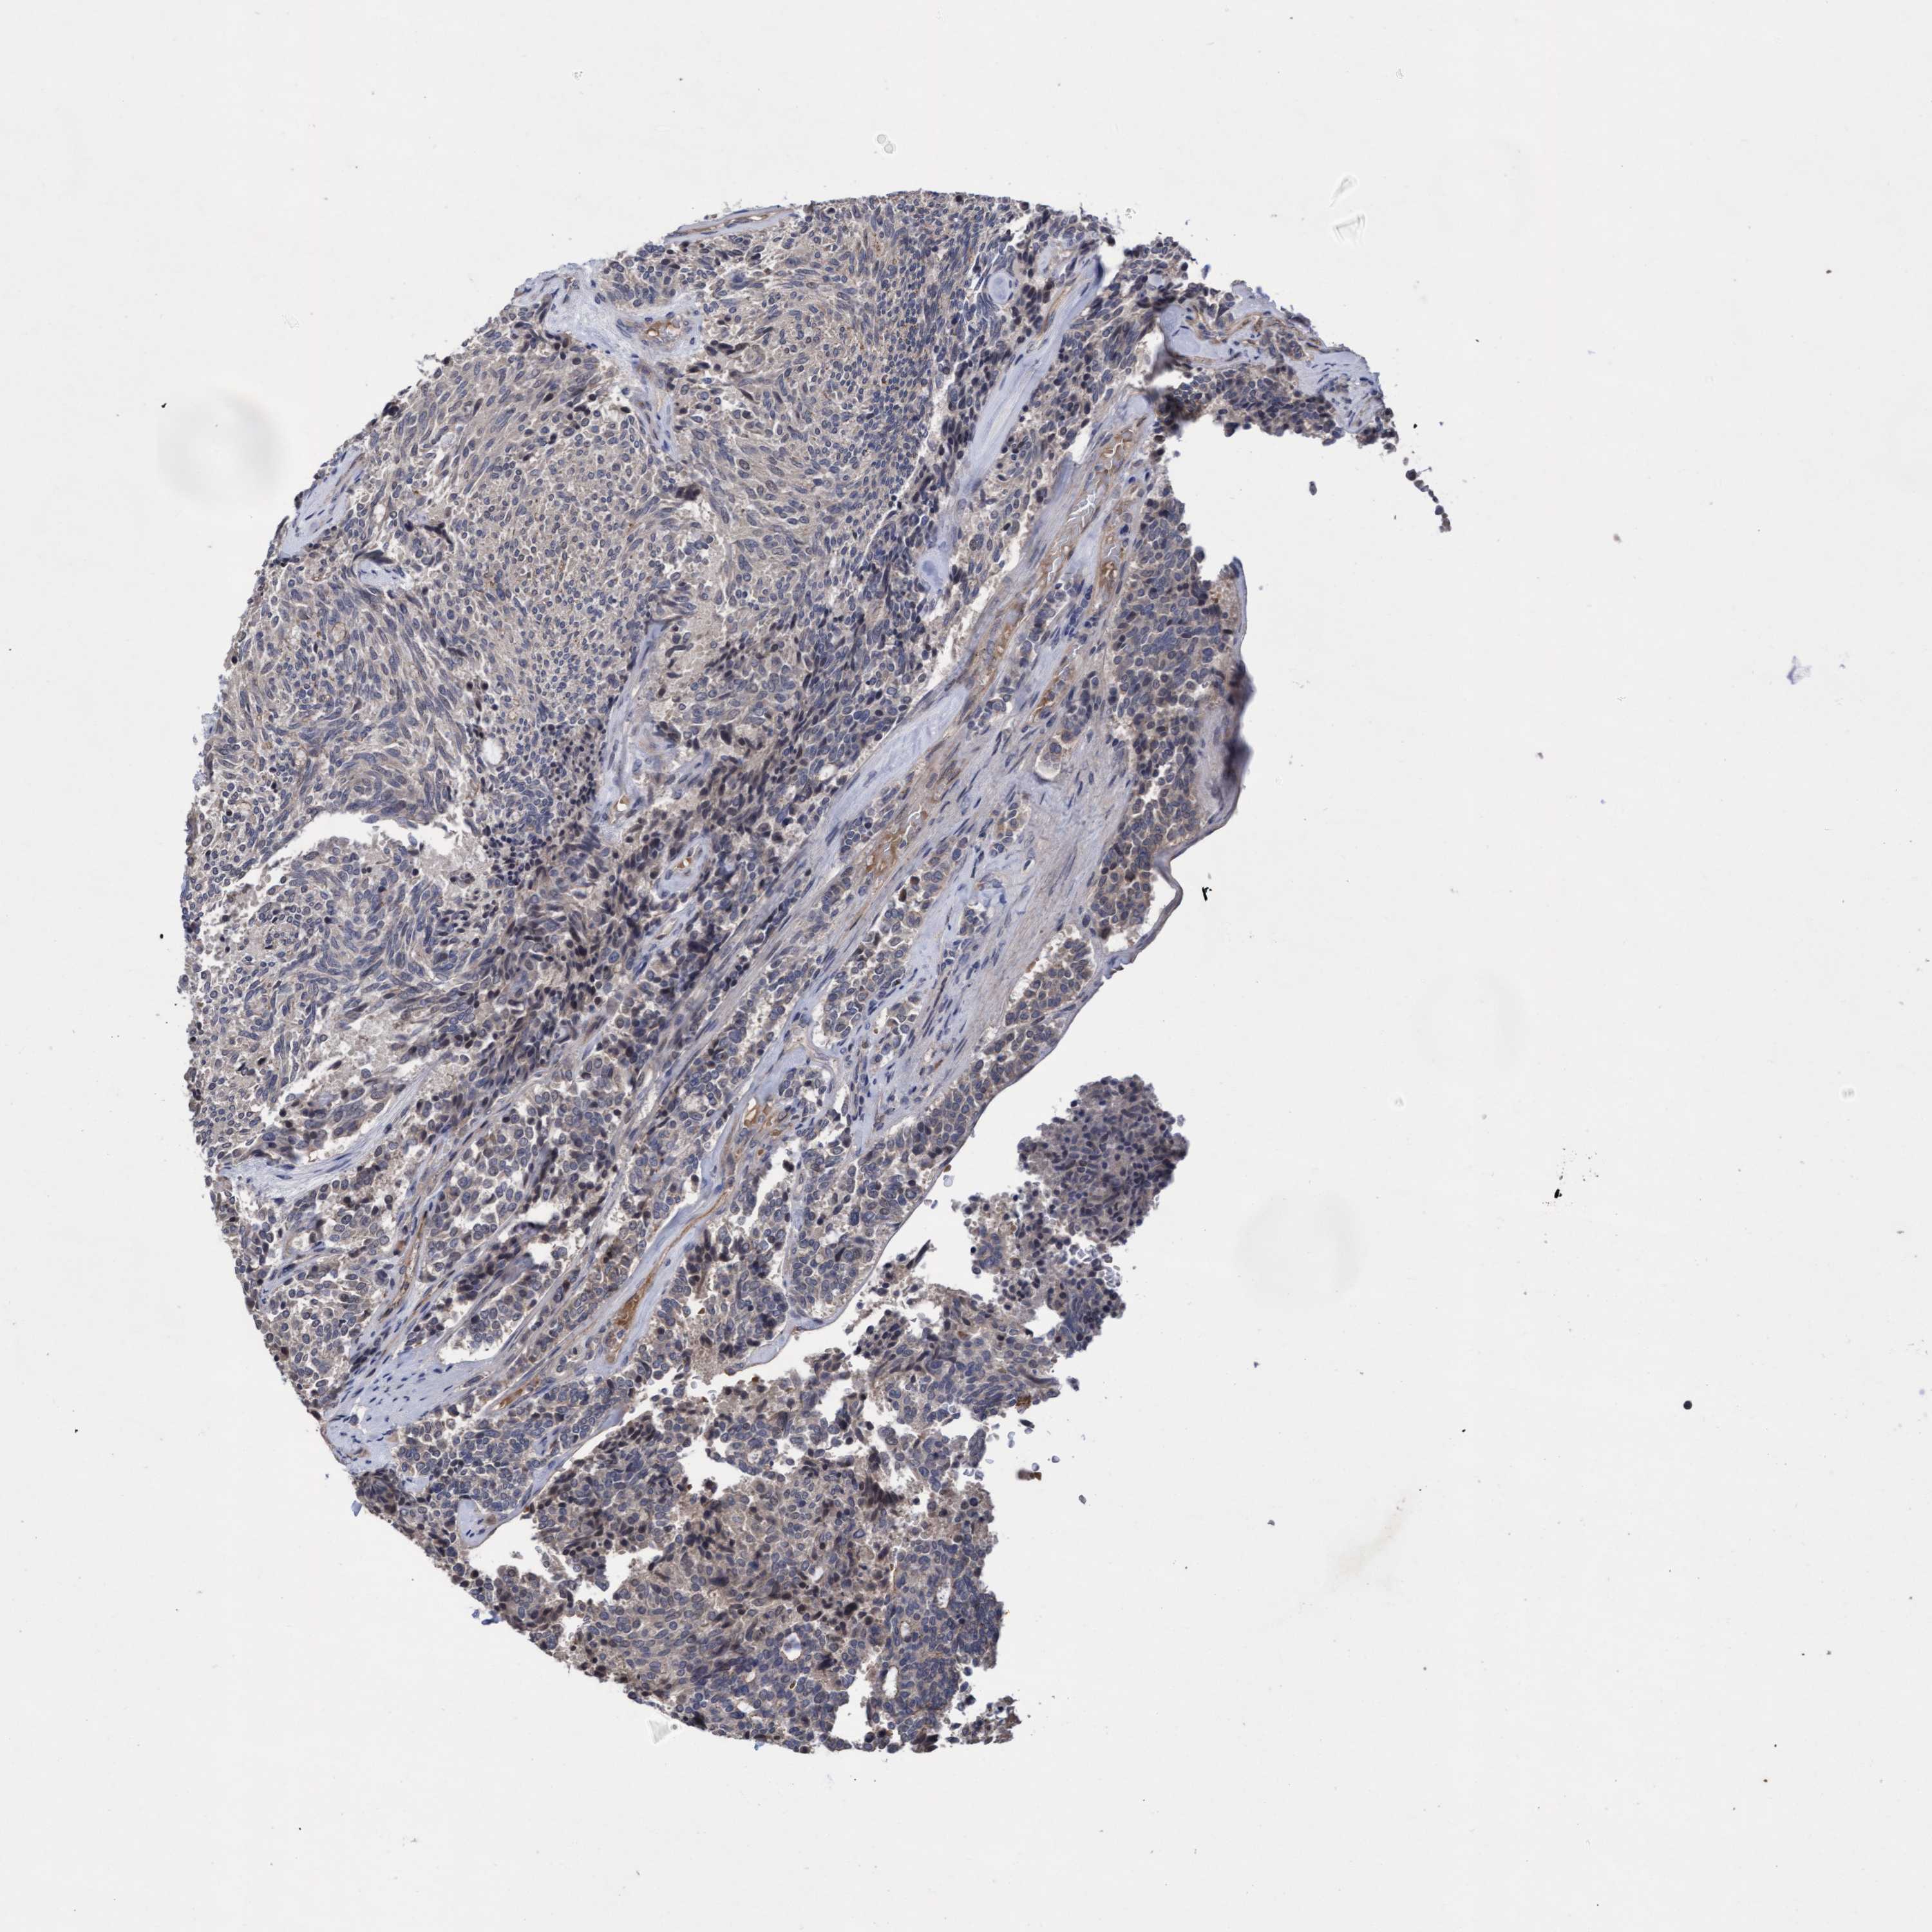

CARCINOID - Protein expressioni

A mouse-over function shows sample information and annotation data. Click on an image to view it in a full screen mode. Samples can be filtered based on level of antibody staining by selecting one or several of the following categories: high, medium, low and not detected. The assay and annotation is described here.

Antibody stainingi

Antibody staining in the annotated cell types in the current human tissue is reported as not detected, low, medium, or high, based on conventional immunohistochemistry profiling in selected tissues. This score is based on the combination of the staining intensity and fraction of stained cells.

Each image is clickable and will lead to virtual microscopy that enables deeper exploration of all samples and also displays staining intensity scores, fraction scores and subcellular localization as well as patient and tissue information for each sample.

Antibody HPA019167

Staining

Medium

Intensity

Moderate

Quantity

75%-25%

Location

Cytoplasmic/membranous

Carcinoid, malignant, NOS